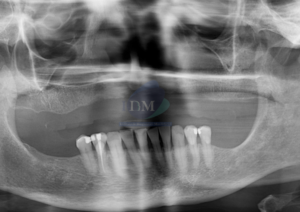

Paciente masculino de 50 años acude al Instituto de Diagnóstico Maxilofacial con el motivo de consulta de una tomografía de haz cónico de campo reducido